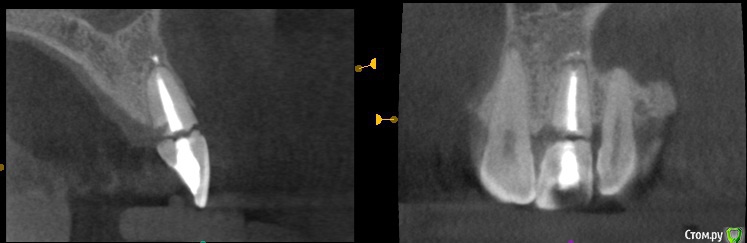

Дмитрий М Опубликовано 25 сентября, 2019 Поделиться Опубликовано 25 сентября, 2019 Пуциент 43г. перелом 21 зуба пациент без эстетических притязаний, совсем. главное, чтобы было дешево )))воксап- удаление - щит- имплантация- изготовление временной- фиксация Ссылка на комментарий

Дмитрий М Опубликовано 27 сентября, 2019 Автор Поделиться Опубликовано 27 сентября, 2019 Хорошая работа ! какой имплантант установлен?спасибо superline 4,5*12 Ссылка на комментарий

annda Опубликовано 21 октября, 2019 Поделиться Опубликовано 21 октября, 2019 Никак не могу понять, зачем такие диаметры в резцы??? 2 Ссылка на комментарий

Дмитрий М Опубликовано 25 октября, 2019 Автор Поделиться Опубликовано 25 октября, 2019 у пациента свои зубы большие, 4,5 проходил с зазором, Ссылка на комментарий